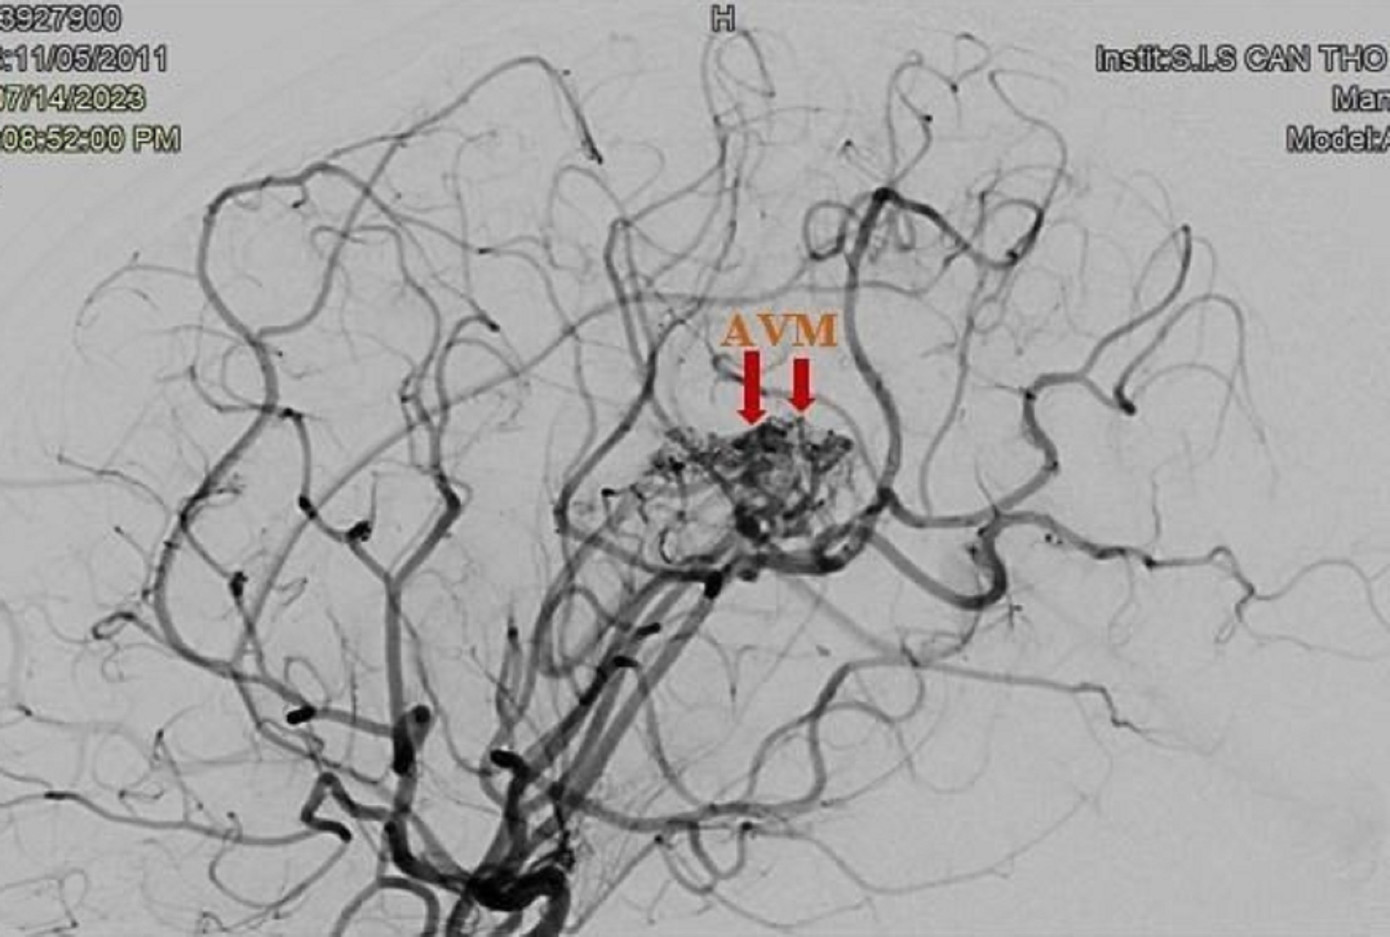

| Túi giả phình mạch máu não của bệnh nhân trên hình ảnh kiểm tra |

BS Ngô Minh Tuấn, Trưởng khoa Chẩn đoán Hình ảnh, Bệnh viện S.I.S Cần Thơ, cho biết, bệnh nhi đã bị xuất huyết não do vỡ dị dạng thông động tĩnh não AVM và có túi giả phình lớn (kích thước 3x3mm) trong búi dị dạng. Đây là tình trạng rất nguy hiểm, các bác sĩ đã tức tốc can thiệp xử lý vị trí mạch máu dị dạng bị vỡ và tắc túi giả phình giúp bệnh nhân qua nguy kịch.